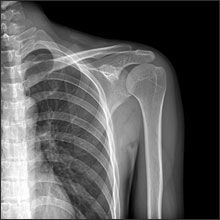

| AP Humerus | humeral epicodyles not in profile radial head, neck and tuberosity to not superimpose ulna arm is externally rotated (greater tubercle in profile) |

| Lateral Humerus | over rotation places the humeral head within the field of the chest |

| Lateral Humerus | epicondyles are not perpendicular humerus is internally rotated (lesser tubercle is in profile medially) overrotation |

| AP Humerus | ANATOMY: entire humerus: shoulder -> elbow CRITERIA: greater tubercle in profile - hand externally rotated humeral epicondyles are parallel to IR POSITIONING: CR perpendicular @ midhumerus |

| Lateral Humerus | ANATOMY: entire humerus: shoulder -> elbow CRITERIA: lesser tubercle in profile - arm internally rotated epicondyles superimposed POSITIONING: pt rotated 15-20 degrees from PA to get arm lateral and away from chest - flex elbow 90 degrees CR perpendicular @ midhumerus |